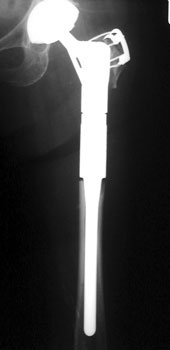

Revision arthroplasty (A). Proximal femur resected due to large amount of osteolysis (B).